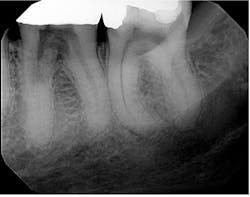

I almost missed this lesion on the radiograph

The distinct radiolucency on no. 25, just below the lower apical half of the tooth, is external resorption. The key diagnostic feature that differentiates it from internal resorption is the fact that the canal is defined. The CBCT confirms this, of course.

The patient presented asymptomatic (as these lesions usually are), and after discussion, we moved forward with a referral for assessment of extent and considerations for anticipated replacement.